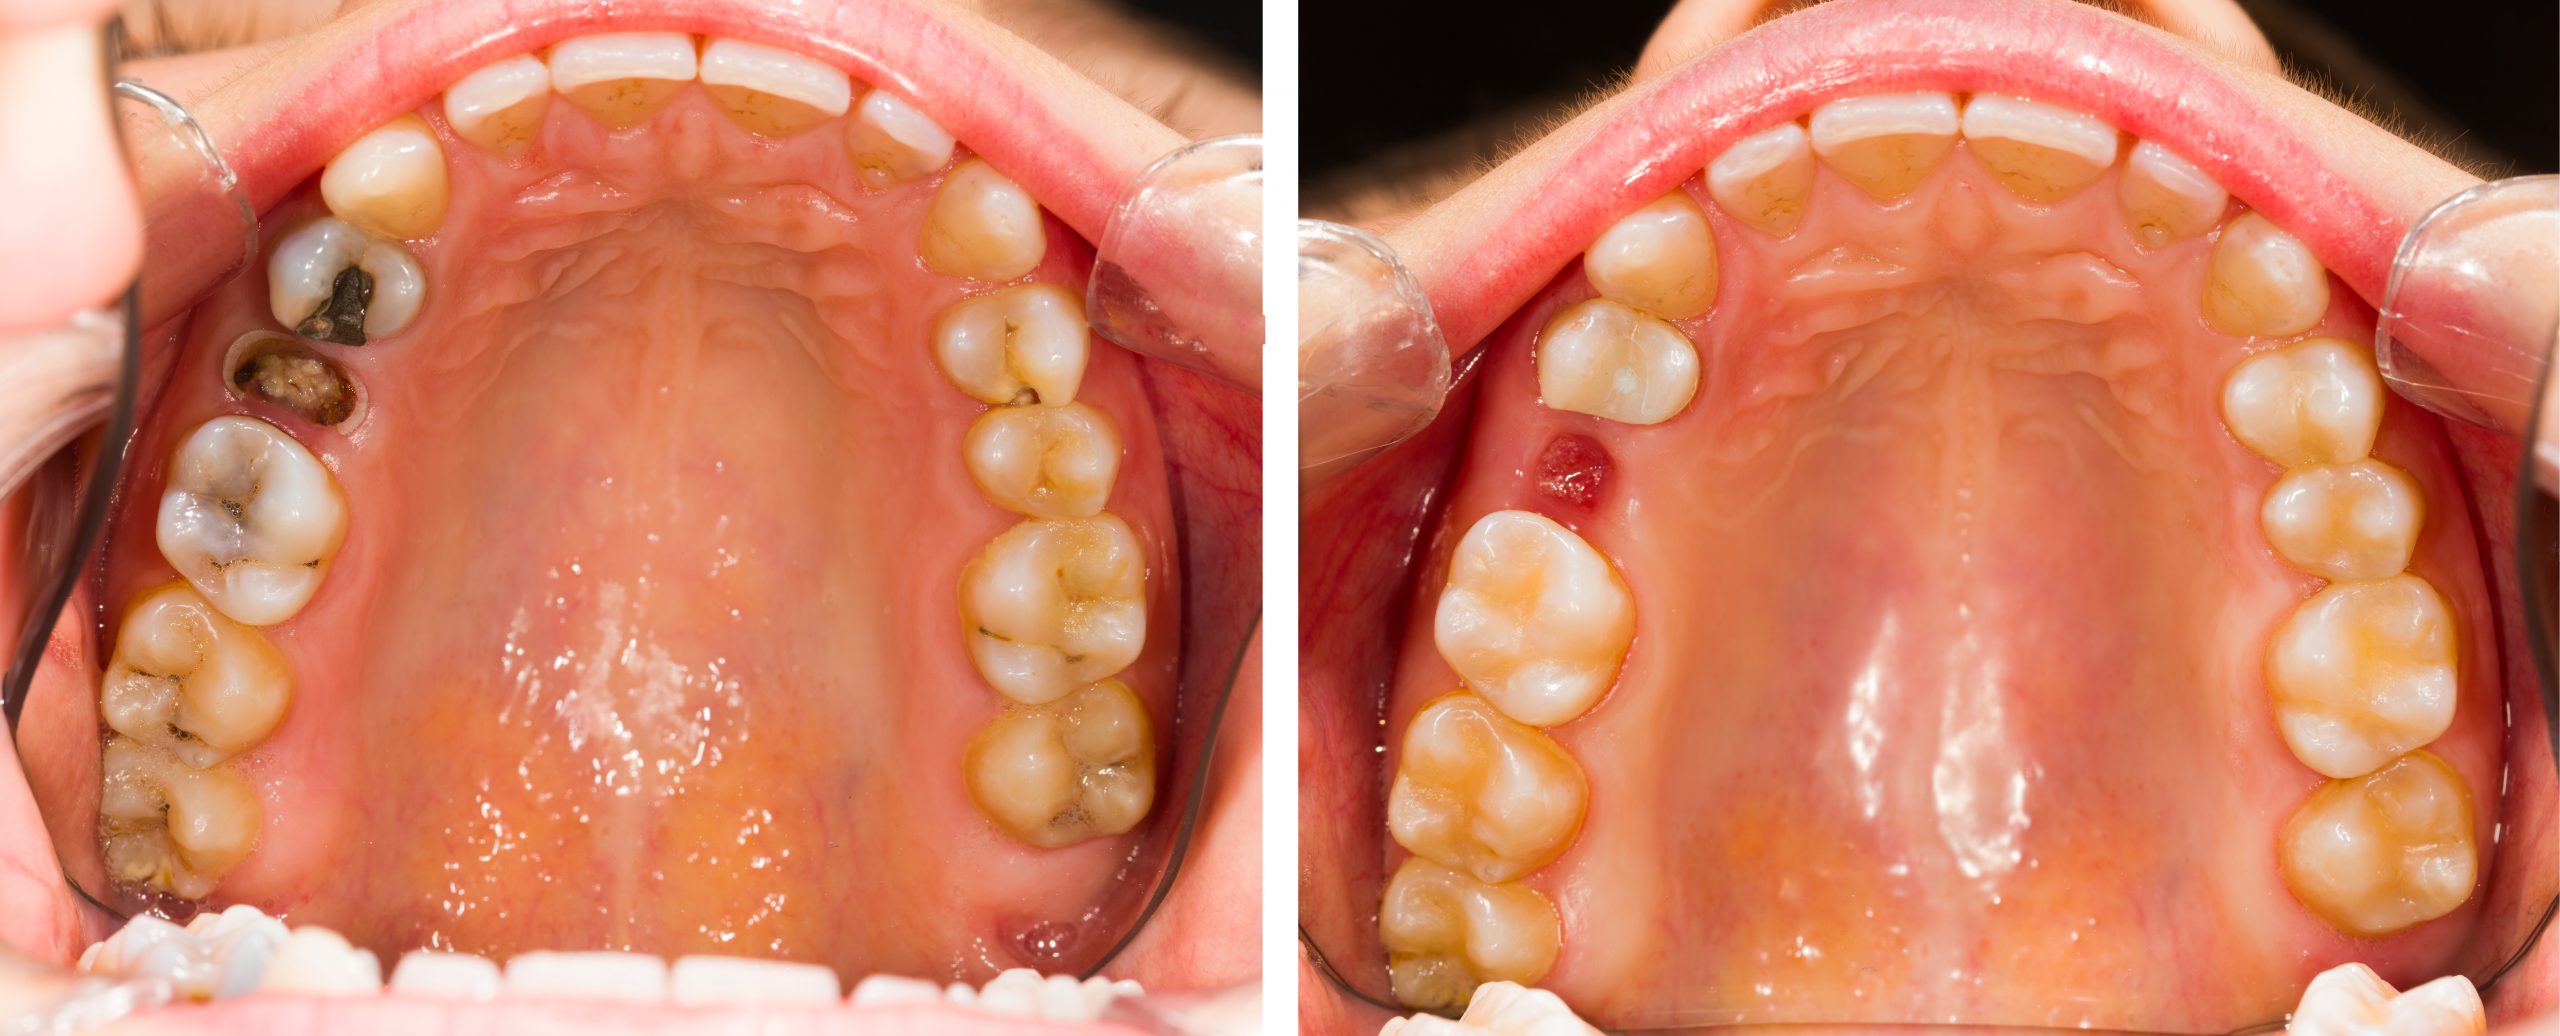

درمان دندان معمولاً با روشهایی مانند ترمیم، عصبکشی یا استفاده از روکشها انجام میشود. اما گاهی شدت آسیب یا عفونت آنقدر بالاست که دندان دیگر قابل نجات نیست. در این موارد، دندانپزشک متخصص تشخیص میدهد که باید دندان کشیده شود.

- پوسیدگی شدید و غیرقابل درمان دندان

- وجود عفونت مزمن که به سایر نقاط دهان گسترش یافته